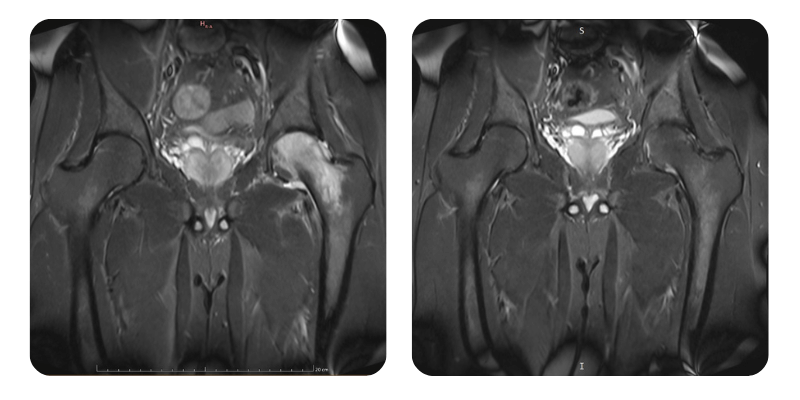

Prima

Dopo

S.A., 32 anni - Necrosi asettica della testa femorale sinistra (NACF), stadio I

Anamnesi: Paziente di 32 anni, con la seguente patologia nota: necrosi asettica della testa femorale sinistra, stadio I secondo Arlet e Ficat. Si presenta in clinica con dolore 3/10 a livello dell' anca sinistra, con sintomatologia insorta circa un mese fa.

Diagnosi: Necrosi asettica della testa femorale (NACF) sinistra, stadio I.

Interventi terapeutici: Ossigenoterapia iperbarica secondo protocollo iniziale di 20 sedute, seguita da rivalutazione RMN.

Evoluzione: Il paziente si presenta alla rivalutazione dopo il primo ciclo di trattamento per NACF stadio I; ha effettuato 22 sedute HBOT senza reazioni avverse o complicanze. Non presenta piu dolore e ha attivita fisica normale.

Prognosi: Buona. Il paziente presenta guarigione completa.